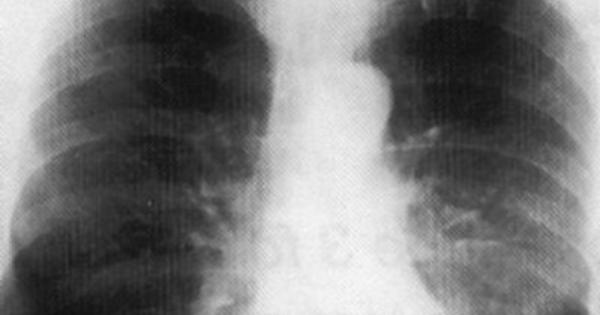

Milano, 3 mag. (AdnKronos Salute) - Per alcuni è una compagna di vita che li affianca da anni. In un primo momento passa inosservata, poi diventa sempre più invadente, fino a lasciare letteralmente senza fiato. E' la Bpco, broncopneumopatia cronica ostruttiva, che ruba il respiro di 2,6 milioni di italiani. Anche di più, se si considera chi ne soffre ma è ancora orfano di diagnosi. Un nemico che può colpire duro, e trova il fumo di sigaretta fra i suoi primi alleati. Per una fetta di questo esercito di 'affannati' - in genere over 65, con una lunga storia di malattia (che è sfuggita di mano) e, in certi casi, altre patologie con cui convivere - anche fare pochi passi in casa diventa un'impresa. Per loro "i sintomi di ostruzione bronchiale e infiammazione, dalla tosse alla dispnea, sono costanti a prescindere dalla terapia che si sta seguendo, le riacutizzazioni frequenti e il ricovero in ospedale un destino spesso dietro l'angolo", spiega Antonio Spanevello, primario dell'Unità operativa di Pneumologia riabilitativa all'Istituto scientifico di Tradate (Fondazione Maugeri), oggi durante un incontro a Milano. Per questi pazienti più gravi, che uno studio stima possano essere il 41% degli italiani con Bpco, oggi c'è un'opportunità terapeutica in più. Una 'triplice terapia' - la prima studiata ad hoc in clinica - che mette sotto attacco il problema da più fronti, sfruttando tre diversi meccanismi d'azione con un antinfiammatorio e due broncodilatatori. Si tratta dell'associazione tra umeclidinio, antagonista muscarinico a lunga durata d'azione (Lama), che si somministra con un device, e fluticasione furoato e vilanterolo (rispettivamente un Ics, corticosteroide inalatorio, e un Laba, beta-2 agonista a lunga durata d'azione) che si somministrano con un altro device. Una tripla arma da 'sfoderare' una sola volta al giorno. La triplice terapia, targata Gsk, "è stata studiata per essere sicura per i pazienti e garantire una copertura di 24 ore", afferma Andrea Rizzi, direttore medico Area respiratoria GlaxoSmithKline Italia. E se al momento viene proposta divisa in due erogatori uguali, "nel giro di un anno e mezzo ce ne sarà soltanto uno, con l'arrivo della triplice terapia 'chiusa'. Il device è semplice e intuitivo: apri, inala e chiudi. E abbiamo appurato che, alla sola lettura del foglietto illustrativo, 99 pazienti su 100 lo usano correttamente". Non basta infatti avere armi 'personalizzate' per pazienti in condizioni severe, se poi come spesso succede l'aderenza alle cure prescritte resta scarsa. L'obiettivo a cui puntano i medici che a più livelli si occupano di malati di Bpco è proprio questo: incidere sul quadro tracciato dalle statistiche più recenti, in base alle quali le terapie vengono assunte regolarmente solo da una persona su due e per non più di tre mesi all'anno, con una situazione ancora peggiore fra gli ultrasessantacinquenni. "Il medico di famiglia può giocare un ruolo strategico - sottolinea Gabriella Levato di Fimmg (Federazione italiana medici di medicina generale) Lombardia - perché segue nel tempo il paziente, conosce tutte le sue patologie e non solo la Bpco. Oggi strumenti moderni come software gestionali di studio ci dicono se un paziente non prende da tanto tempo un farmaco, e nell'armamentario terapeutico disponibile si può scegliere la soluzione più adatta alle caratteristiche e alle capacità di quella specifica persona". Per Gioacchino Nicolosi, vice presidente vicario di Federfarma, "anche il farmacista può fare la sua parte, captando eventuali difficoltà del paziente, spiegando i device, aspetto per il quale ci vengono in aiuto anche programmi ad hoc per far visualizzare il funzionamento su uno schermo. Serve gioco di squadra con i professionisti coinvolti nella cura del paziente". E se è vero che il ritorno in ospedale per una riacutizzazione della Bpco "è da considerarsi un fallimento del sistema di gestione del malato in generale, d'altro canto può costituire un momento di start up, di efficienza e sostenibilità. Un'opportunità", fa notare Marco Candela, direttore del Dipartimento di medicina dell'ospedale di Fabriano (Ancona). "Questo - aggiunge l'esperto - avviene favorendo non solo la prescrizione del farmaco giusto al paziente giusto, ma anche altre misure fondamentali: la ginnastica respiratoria, l'attività fisica, un self management strutturato, la profilassi vaccinale e così via. Tutto questo può essere condensato in una scheda di dimissione strutturata sulla Bpco che sia il miglior passaggio di testimone al medico di medicina generale", che potrà continuare a gestire il paziente sul territorio avendo a disposizione tutte le informazioni su quanto avvenuto 'in corsia'. In questo quadro, conclude Spanevello, "una terapia farmacologica come la triplice terapia deve essere la base per prendere il paziente severo, un paziente che è ormai immobile per la mancanza di respiro, e renderlo capace di tornare a uno stile di vita sano che includa come momento fondamentale proprio l'attività fisica, fattore in grado di migliorare persino la sopravvivenza. Uno studio ha mostrato che, dopo 10 anni di Bpco, la muscolatura del quadricipite è nettamente inferiore rispetto a quella di una persona normale. Ecco, noi vogliamo far capire ai pazienti che non sono condannati a una vita fatta di cruciverba e immobilità. Con la terapia giusta, devono tornare a muoversi. Altrimenti, qualunque sforzo non sarà servito a niente".